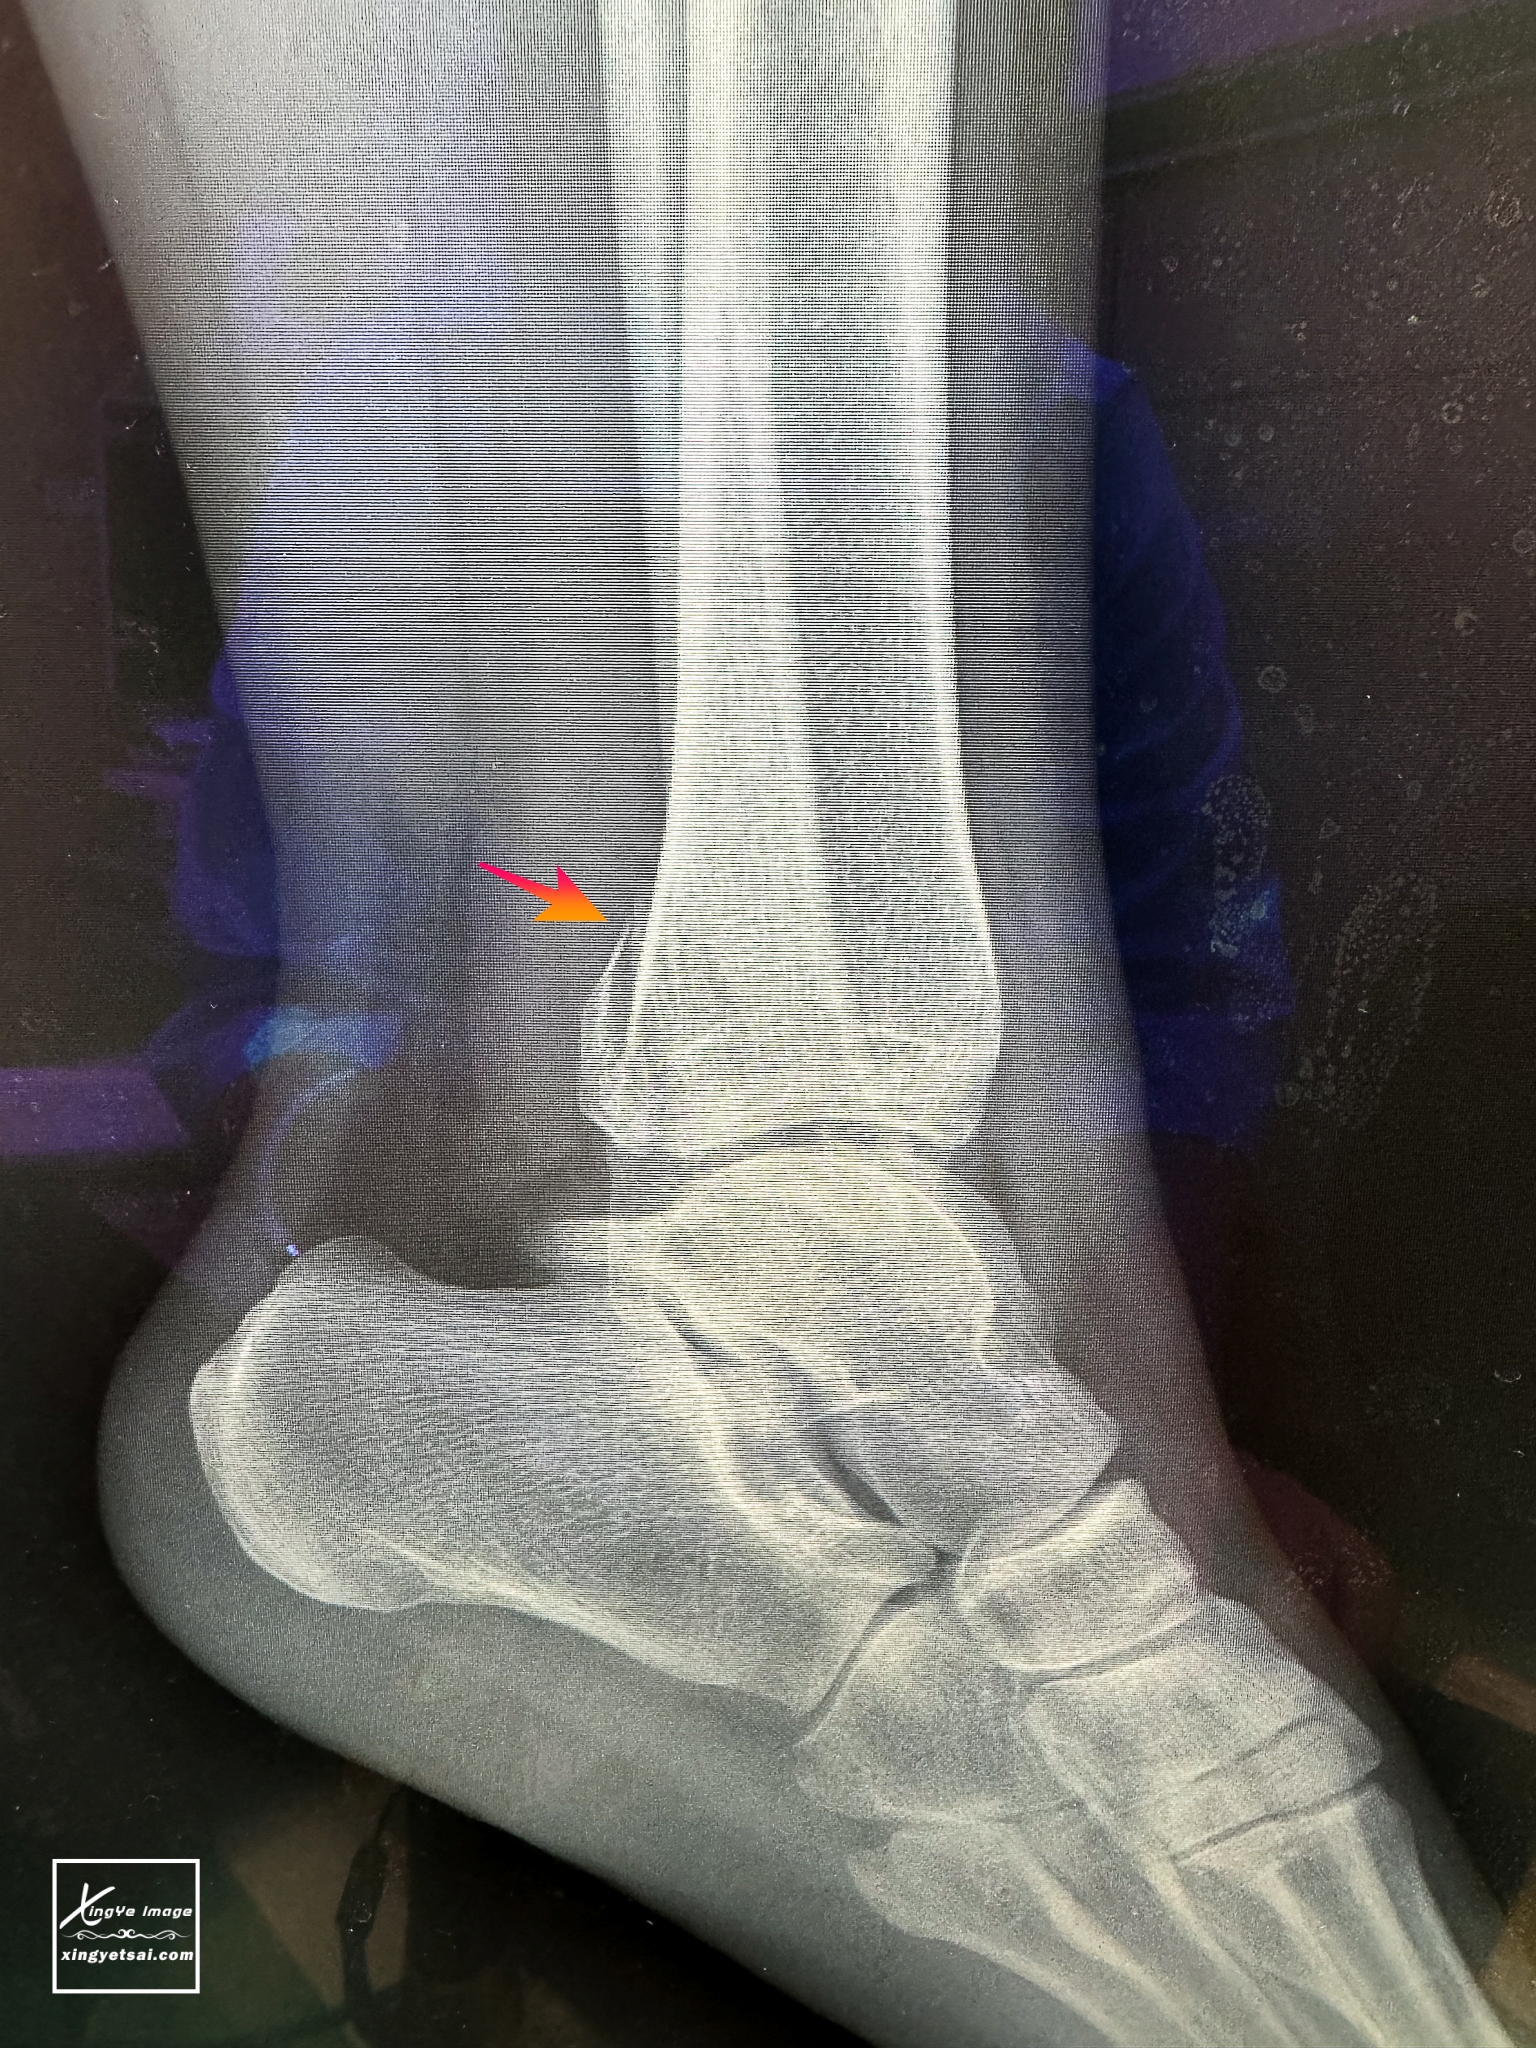

在急診照了X光,左踝關節三踝骨骨折,醫生說傷的挺嚴重,因為左踝關節的左側、右側與後踝都裂了。急診骨科醫師評估需開刀行內固定,自費鈦合金鋼板兩片(一根骨頭需一片),光自費兩片鋼板耗材費用NT$111700,別吃驚,這已經是最便宜的了,以前沒特別在意,竟不知道原來骨傷這麼貴

▲三踝骨折:三踝骨折是一種踝關節的骨折,涉及外踝、內踝和後踝,簡單來說是指腳踝處同時發生內、外、後踝三處都骨折